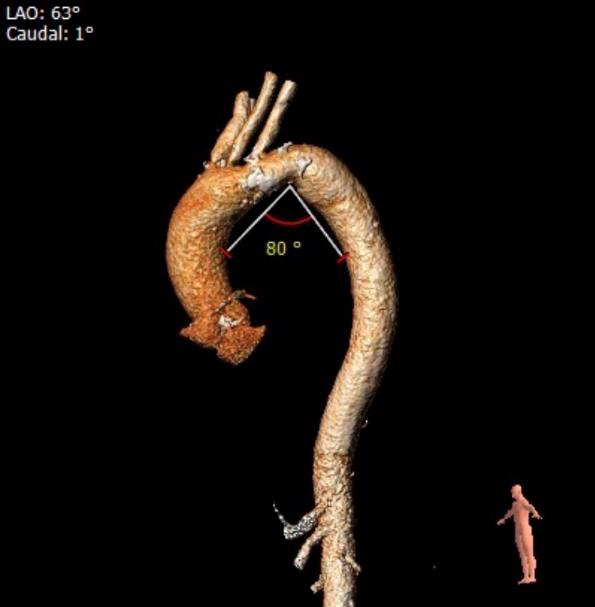

瓦氏窦内径可、窦管交界内径可。升主内径可,主动脉瓣环与水平面夹角可,主动脉弓角度与宽度可。

主动脉根部评估:

瓣环上解剖及钙化分布:

①瓦氏窦整体形态偏大,且伴有主动脉瓣中度关闭不全。

②无冠瓣瓣叶钙化程度较重,结合瓣上结构的特点,较大可能影响瓣膜植入后的形态及贴壁性,瓣周漏发生的风险偏高。